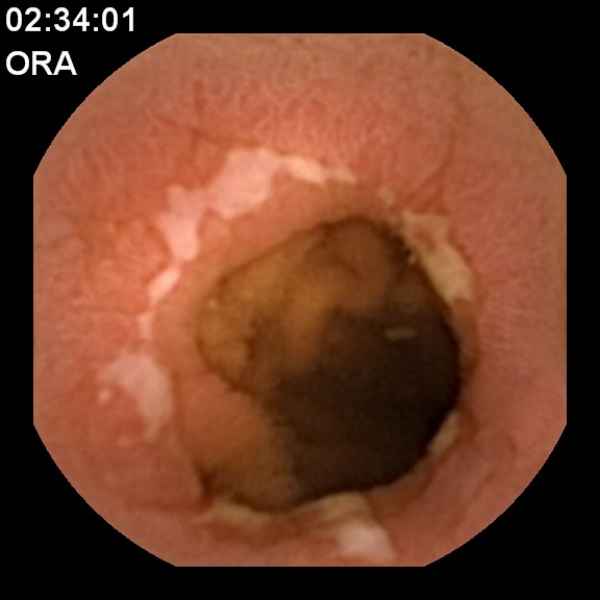

Cálculo impactado no coto cístico - tratamento por litotrícia guiada por colangioscopia

Fotografia